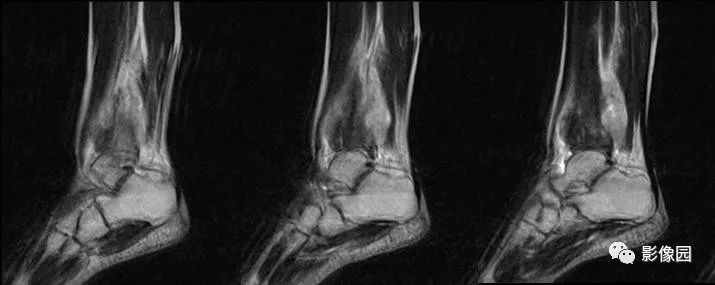

评论:前片X线示左胫骨下段及干骺端病变,髓腔内密度不均匀增高,内侧骨皮质可见骨质破坏,可见骨膜反应。CT示病灶内见多发斑片状肿瘤骨(黄色箭头),周围可见针状骨膜反应(红色箭头)。周围软组织肿胀。MRI示胫骨下段以长T1、长2信号为主的混杂信号影,未跨越胫距关节面,周围未见明显软组织肿块。周围软组织广泛片状长T1长T2信号影。复查X线示病变较前片明显进展,左侧胫骨远段及干骺端骨质破坏,周围可见针状骨膜反应及Codman三角(蓝色箭头)形成。相邻左侧腓骨下端、距骨滑车受累。